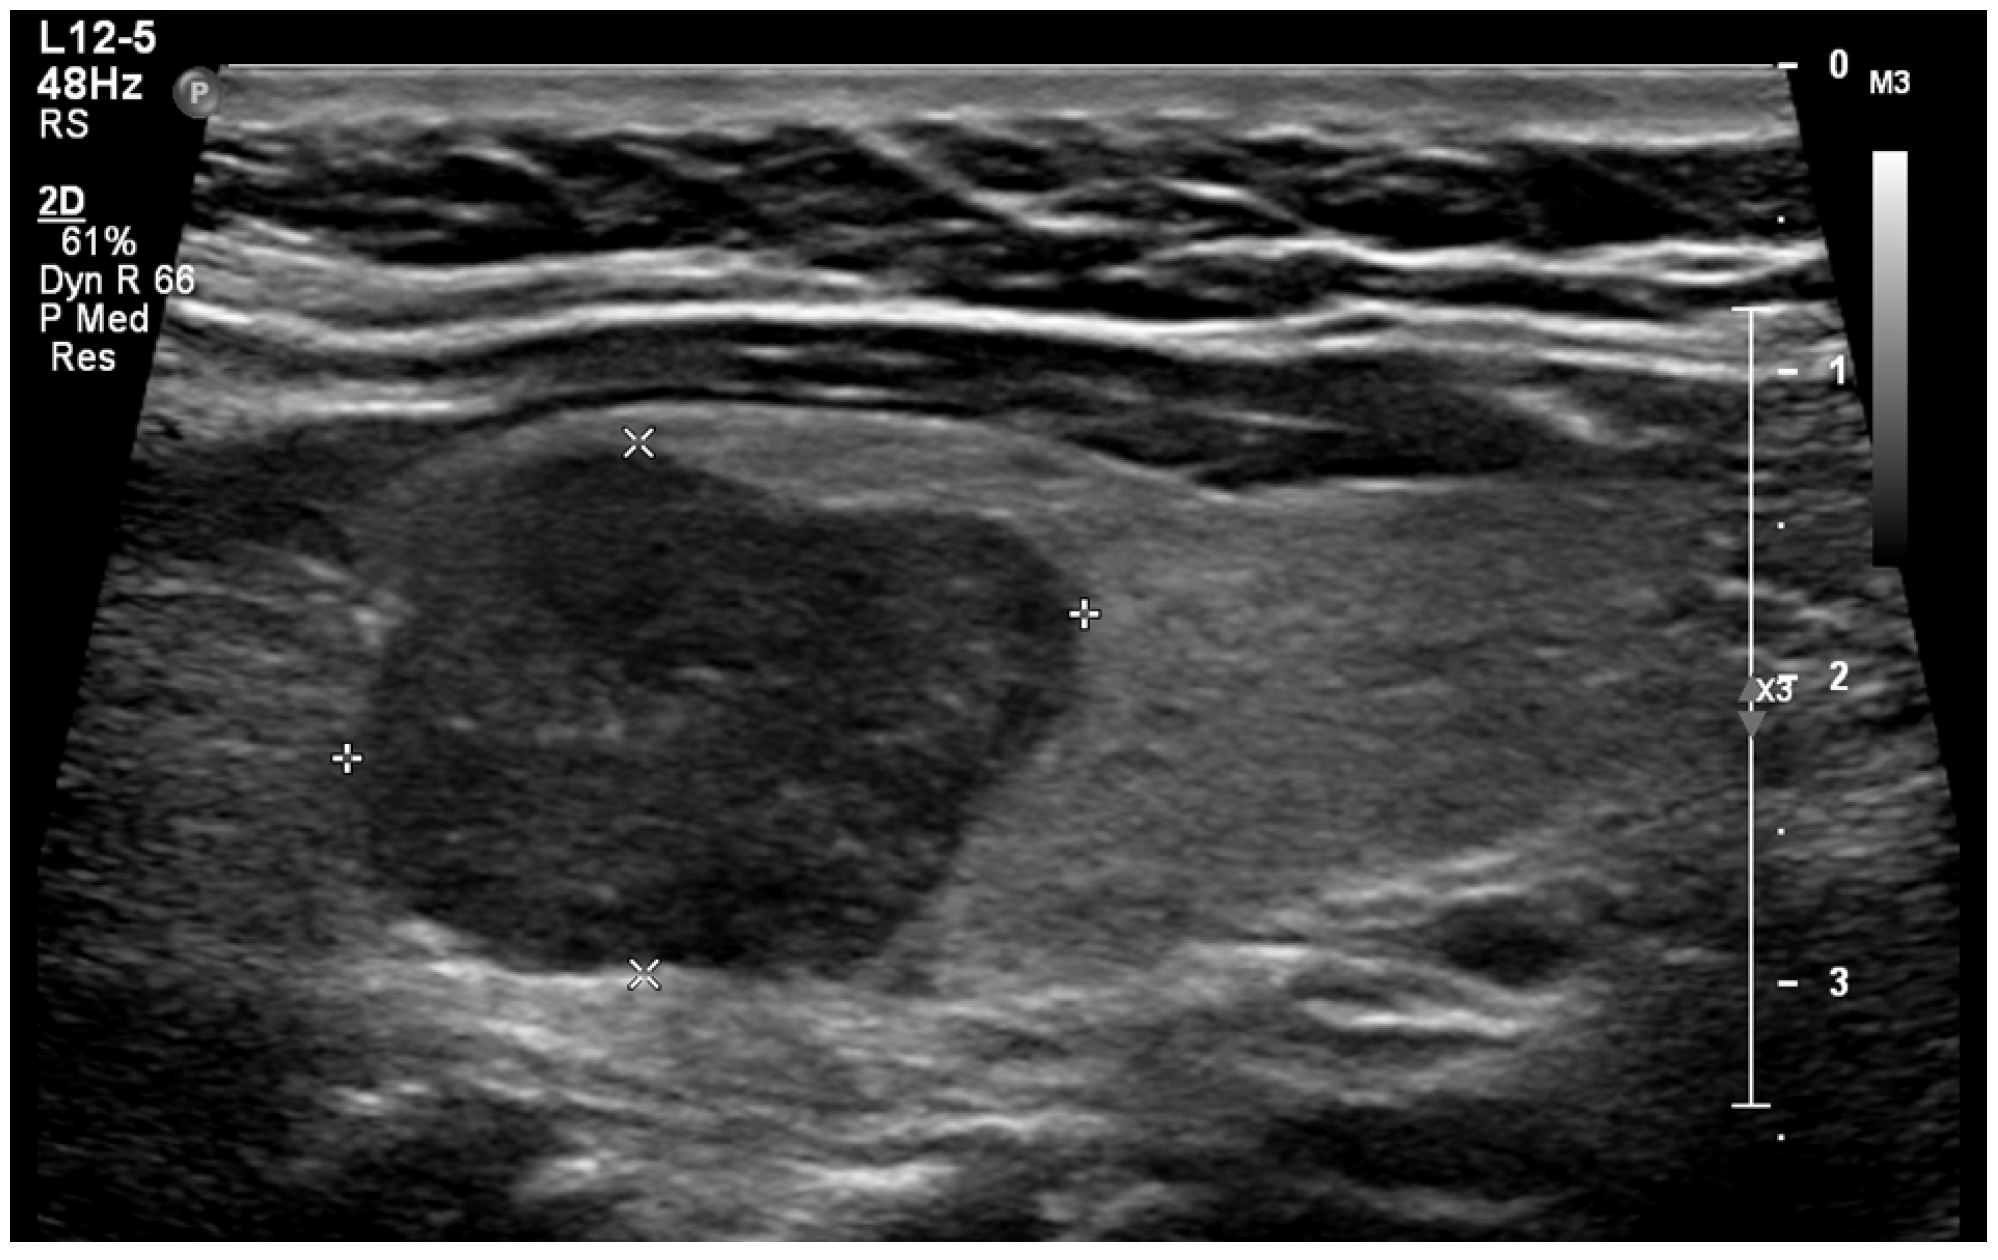

Extrathyroidal extension beyond the thyroid capsule into the surrounding soft tissues is reported in 5% to 34% of thyroid cancers and is a predictor of negative outcomes (Figure 5) [58,59,60]. Detecting minimal extrathyroidal extension, indicated by subtle capsular disruption, is challenging. Additionally, ill-defined benign nodules located near the thyroid capsule may cause focal bulging and capsular distortion, leading to false positives. Consequently, there is considerable interobserver variability in detecting extrathyroidal extension [61]. Lee et al. found that the combination of tumor disruption of the capsule—manifesting as a loss of the capsule’s outline—and >50% tumor contact with the capsule had 95.4% specificity, 23.7% sensitivity, and an AUROC of 0.64 for predicting extrathyroidal extension [25,62]. Our study found that 0.2% of benign nodules were misclassified as showing extrathyroidal extension. In contrast, extrathyroidal extension was found in 8.2% of malignant nodules. Overall, suspected extrathyroidal extension was associated with an OR for cancer of 27.2 (95% CI, 4.6 to 160), at p < 0.001.

Figure 5. Extrathyroidal extension (*) extending anteriorly from a malignant nodule (A).